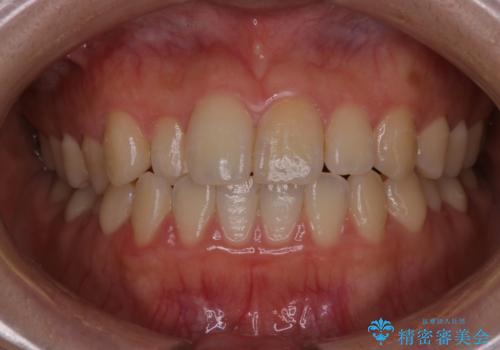

【非抜歯】インビザラインで正しい噛み合わせを

【インビザライン】がたつきをマウスピースできれいにしたい

【インビザライン】かみ合わせを整えたい